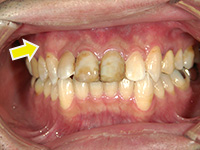

結合組織移植術

右上3番、4番の歯の根が露出していたため、上顎の裏側から結合組織を移植しました。

他の箇所とかわりなく、きれいな歯ぐきになりました。